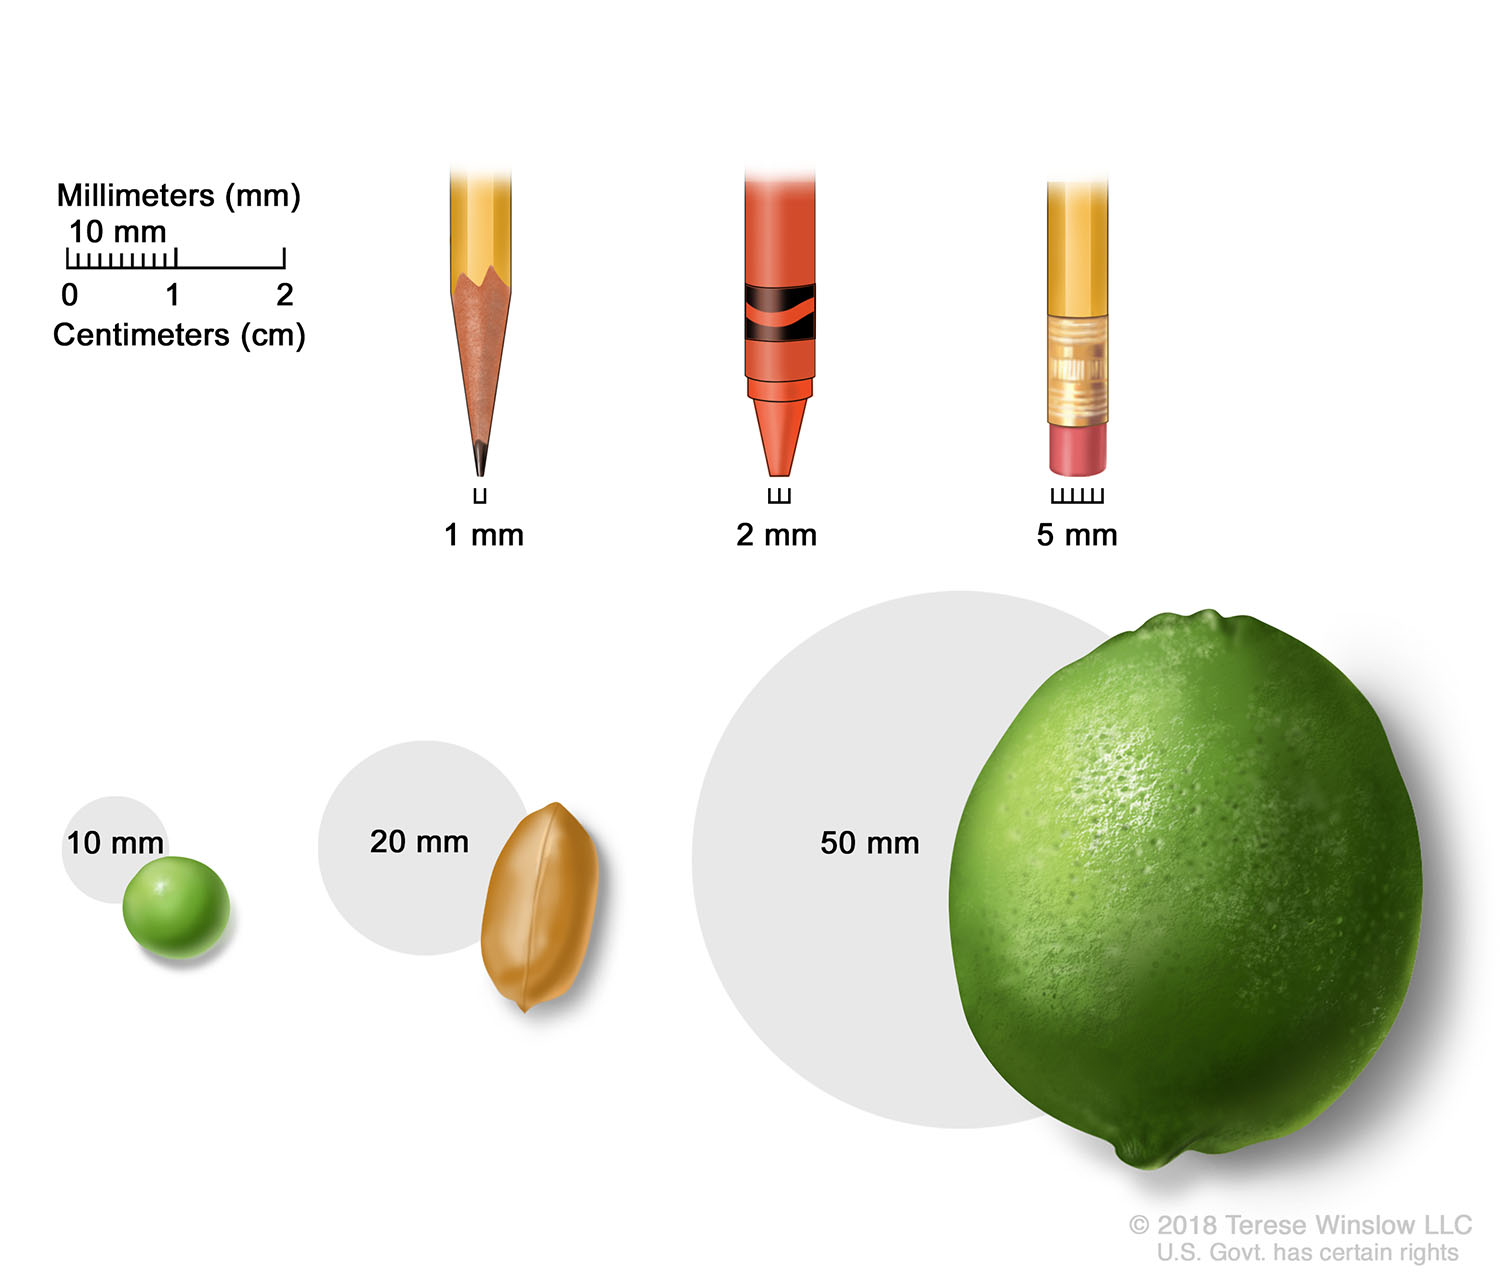

Breast Terese Winslow LLC Medical And Scientific Illustration

https://images.squarespace-cdn.com/content/v1/59b97dbfd2b857017400e500/1562174850181-Z72LG7JY6VPF2MZSD67A/tumor-sizes-millimeters-centimeters.jpg?format=1500w